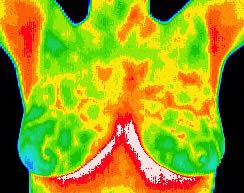

Normal thermal pattern